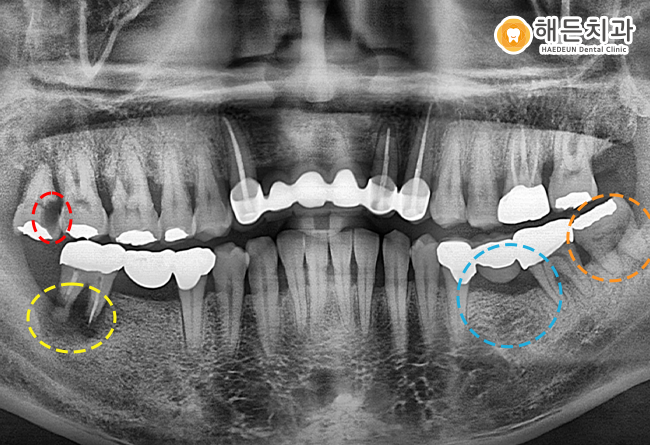

해든치과에서의 치료 후 파노라마 사진입니다.

환자분과 충분한 상담을 통해 치료 계획을 수립하고, 치료를 진행하였답니다.

오른쪽 위의 가장 후방의 사랑니를 발치하였고,

왼쪽 아래 사랑니도 발치를 깨끗하게 마무리 한 것을 확인하실 수 있습니다.

또한 아래쪽에 임플란트 치료도 잘 마무리 되었습니다.

그리고 자주색 동그라미 표시를 보시면, 해당 치아는 상태가 좋지 않았지만

치아를 살리기위해 신경치료를 진행하였는데요.

신경치료를 했음에도 불구하고, 치아의 예후가 좋지 않아 결국 발치를 진행하기로 했습니다.

신경치료를 진행했던 해당 치아를 발치하고, 임플란트를 식립한 모습입니다.

현재 파노라마 사진에는 치아 뿌리 역할을 하는 임플란트 픽스처만 식립된 상태인데요.

픽스처가 잇몸뼈에 잘 유착될수있도록 약 4~6개월 정도 기다린 후

치아 머리 역할을 하는 상부 보철물을 올려주게 됩니다.